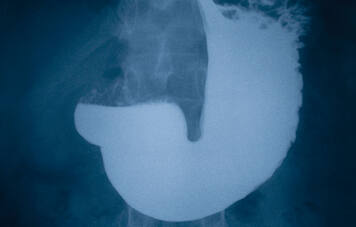

ONCOLOGIA

Concentração de DNA no suco digestivo pode auxiliar na detecção de câncer gástrico Por